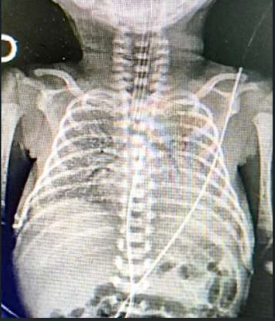

RN nasceu de parto vaginal, com APGAR 5 e 6, apresentando desconforto respiratório de imediato, caracterizado por gemência, tiragem subcostal e taquipneia. A idade gestacional pela DUM foi de 31 semanas. RN foi levado à UTI neonatal, com piora importante do desconforto respiratório, necessitando de intubação orotraqueal. Neonatologista solicitou RX de tórax (imagem abaixo).

Genitora relatou perda de líquido vaginal um dia antes do parto, porém, como foi em pequena quantidade e não teve contrações, decidiu ficar em casa. Somente foi à maternidade 20 horas após a ruptura das membranas, em função da forte intensidade e da elevada frequência das contrações. RN nasceu cerca de duas horas após admissão da gestante na maternidade. Dados pré-natais: Gesta IV/ Aborto II. O cartão da gestante mostrou apenas quatro consultas, com exames realizados somente no primeiro trimestre (todos normais). Sobre esse paciente, assinale a alternativa CORRETA.